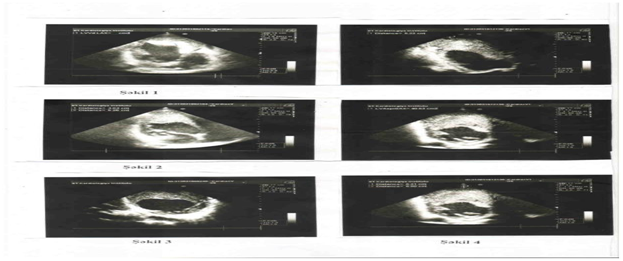

İnfarktdan sonraki anevrizmalı xəstədə ürəkdaxili törəmə Dərc edilib: Cild 9, Nömrə 1, 2016 / Nəşr tarixi: 31.05.2016

E.Z. Ələkbərov, V.M Məmmədrzayeva